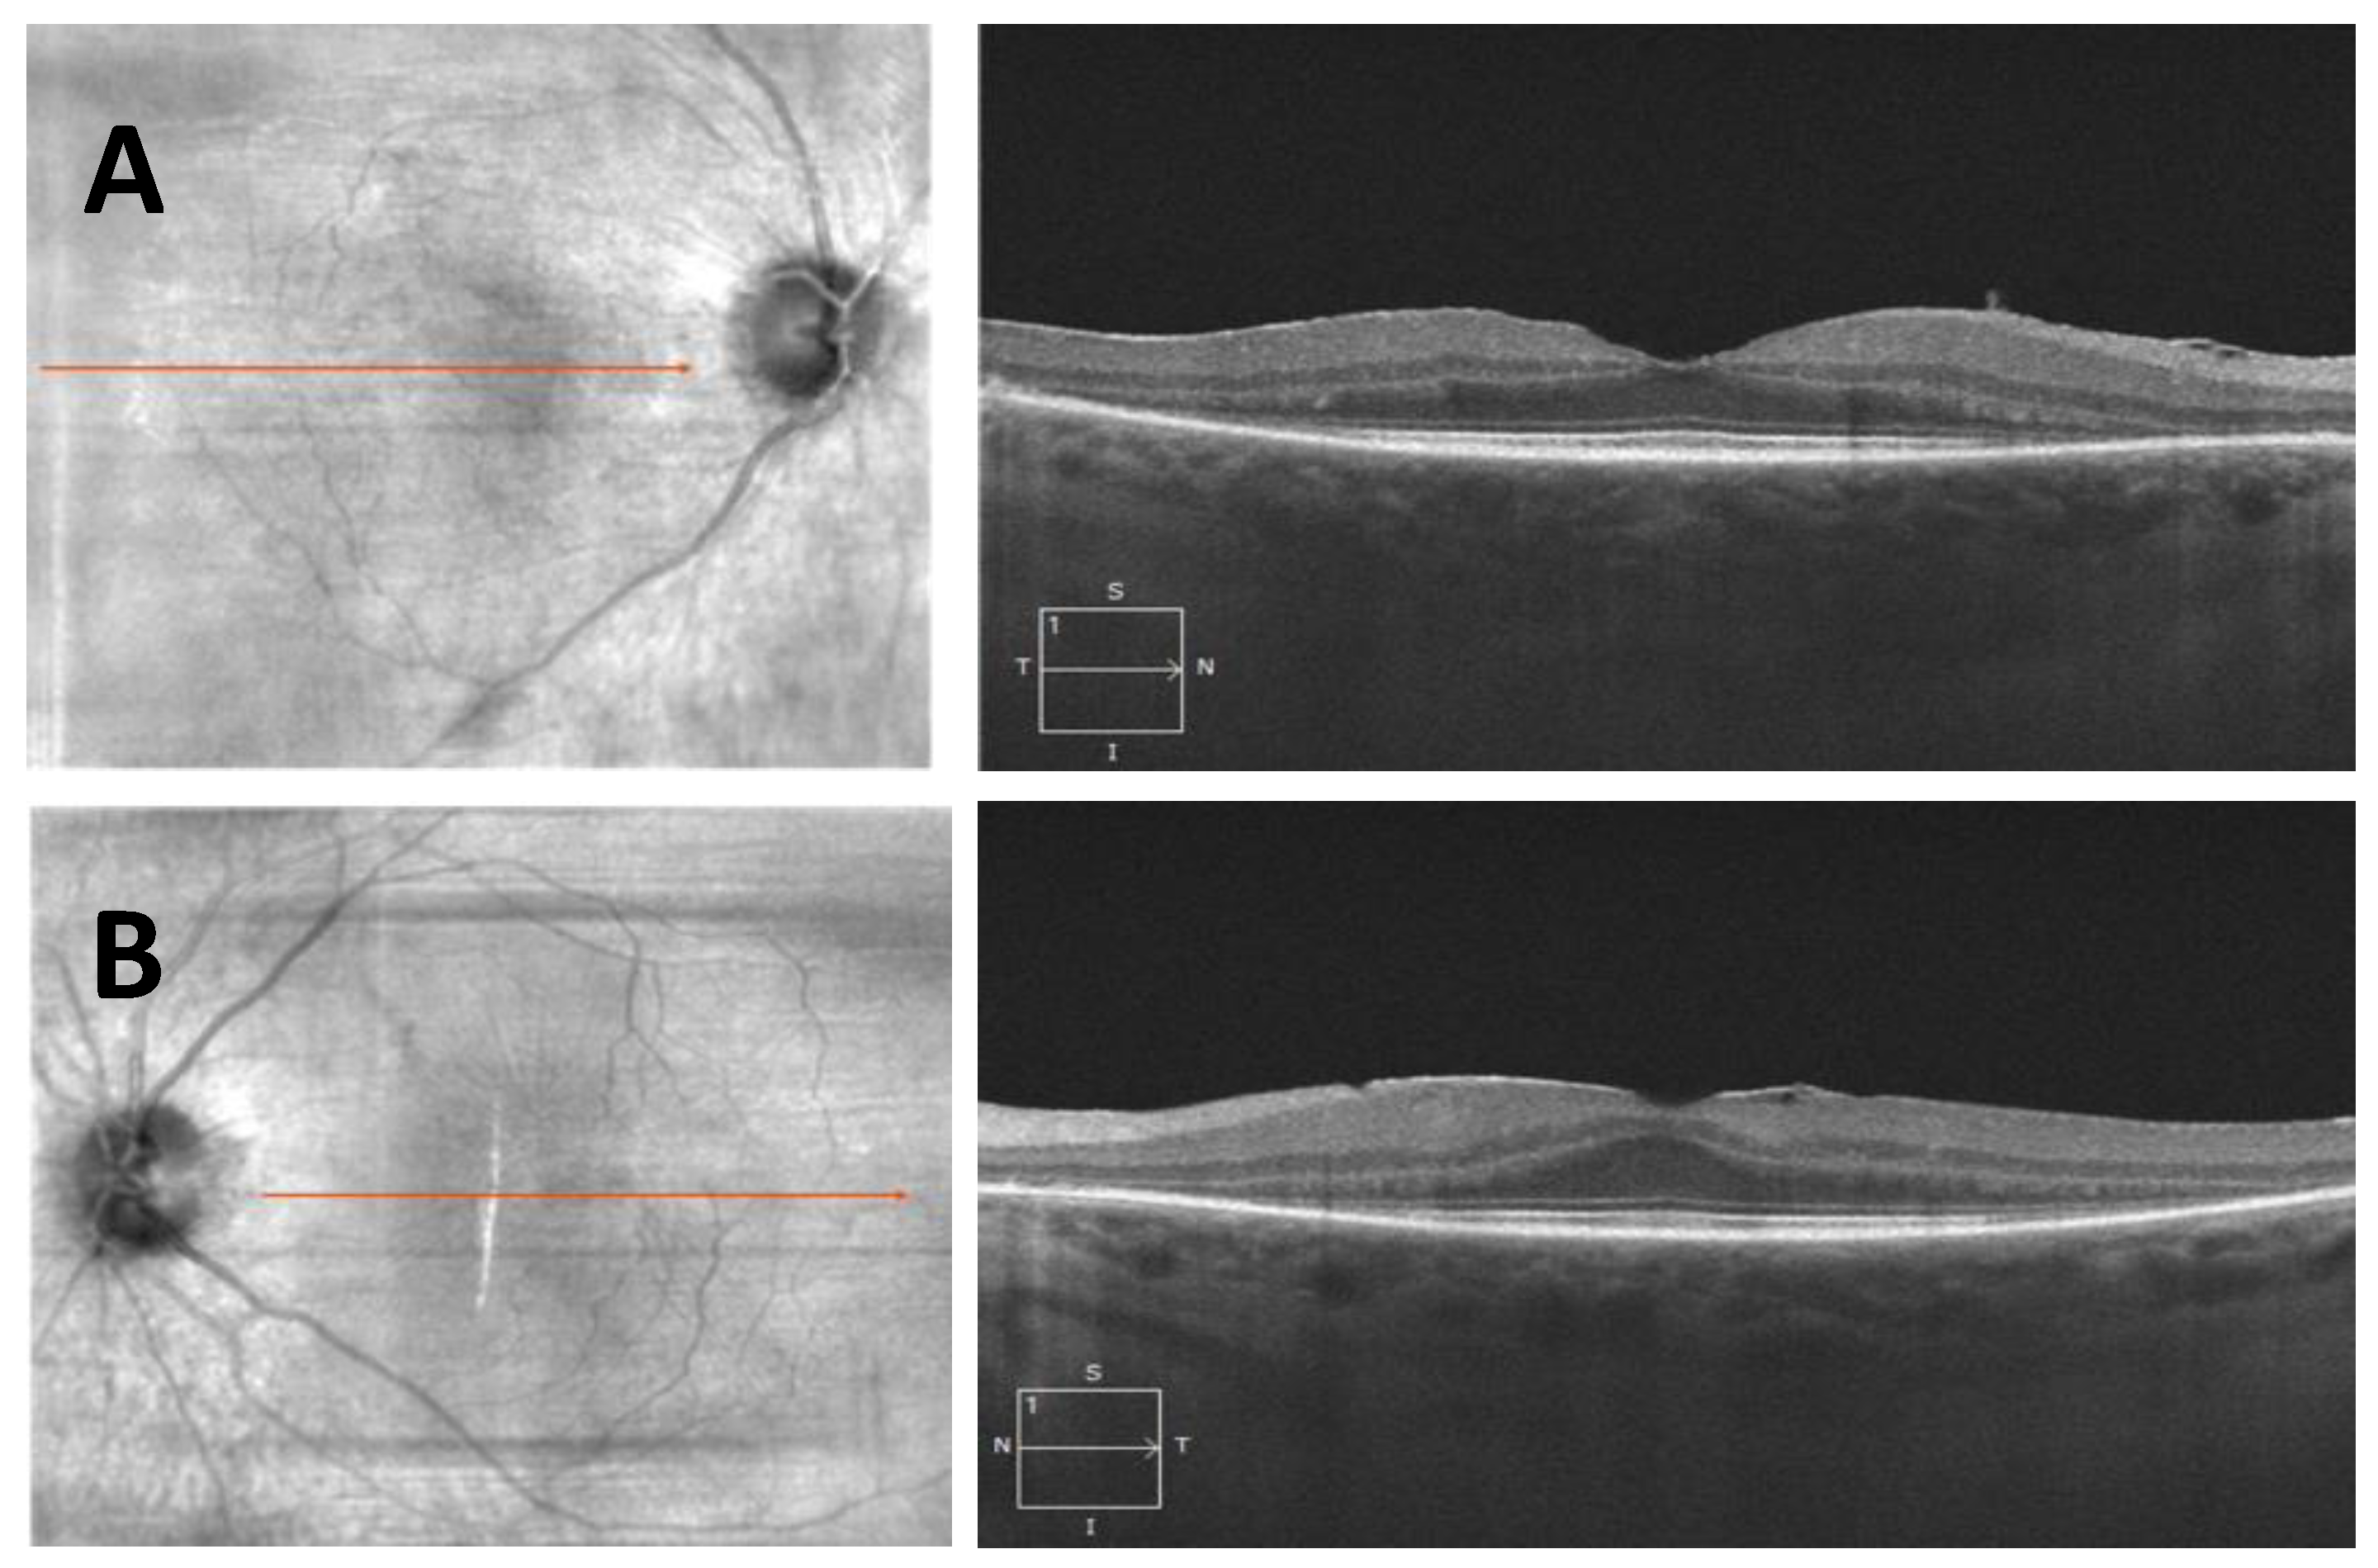

- Case 1:

- Case 2: